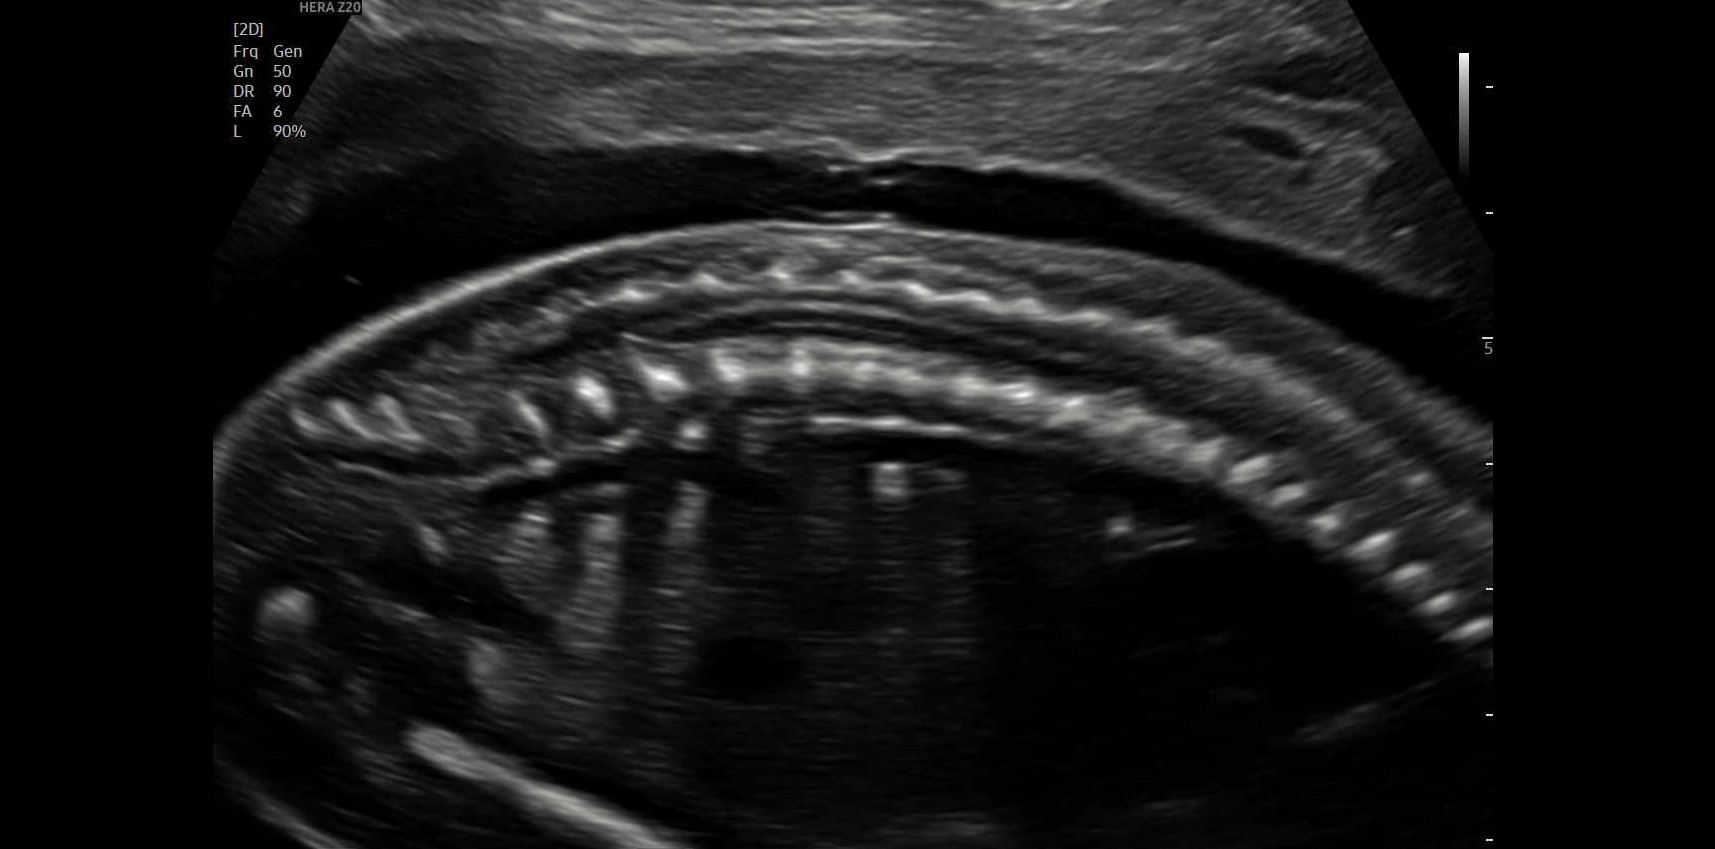

Ersttrimester-Screening: 12-13 SSW

In diesem detaillierten Ultraschall können wir neben der Nackentransparenz bereits die vollständig angelegten Organe Ihres Kindes untersuchen. So erhalten Sie schon früh einen bildlichen Eindruck der ersten Entwicklungsschritte.